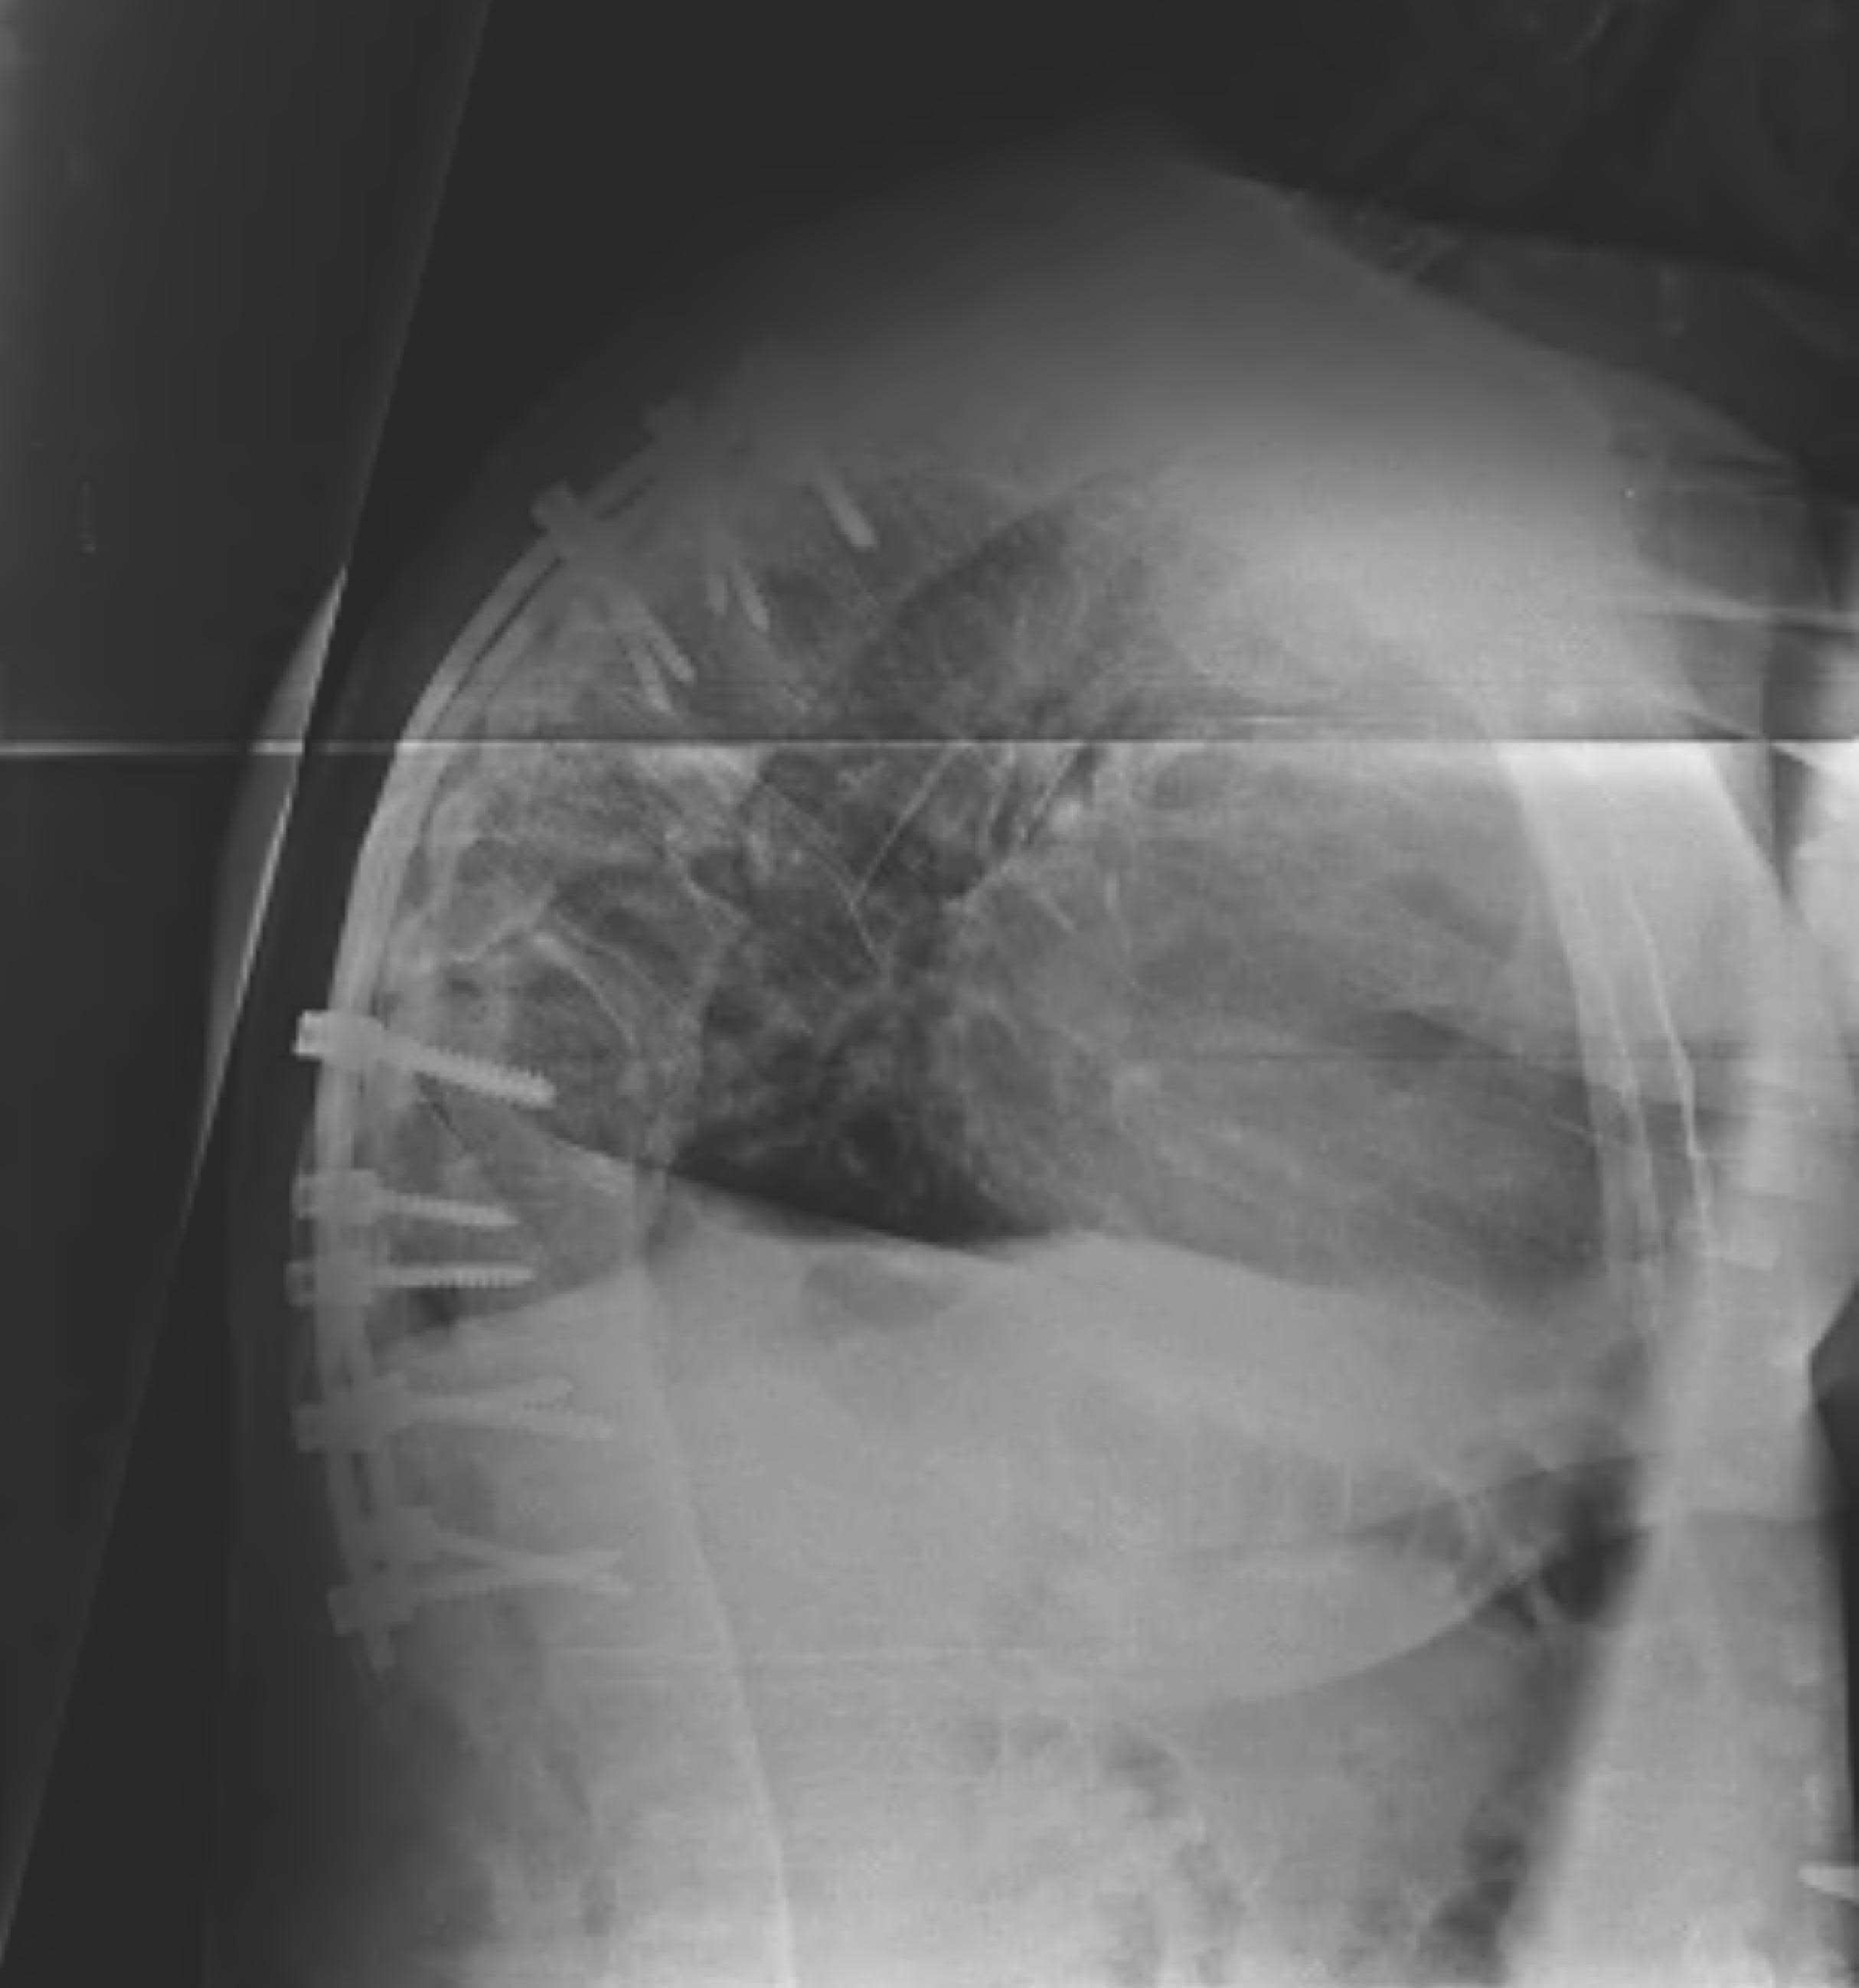

Spine

- marginal erosions / squaring of anterior body concavity

- marginal syndesmophytes

- bamboo spine

D. Bamboo spine

- fusion / bony disc casing

C. Marginal syndesmophyte

- with repeated episodes forms thin vertical bone due to ossification of annulus fibrosis